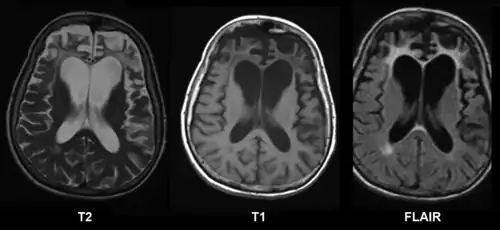

| |

É feito por uma combinação de análise dos sintomas comportamentais, de preferência com algum teste psicológico específico validado no país, associado a técnicas de neuroimagens como EEG ou ressonância magnética. Exame dos fluídos do sistema nervoso central por punção lombar pode ajudar a confirmar o diagnóstico.[1]